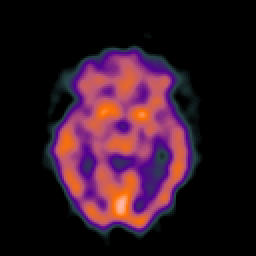

SPECT TC Study #7 -- Slice #25

[Home][Help][Clinical][Tour 1][Tour 2][Tour 3] Slice 25